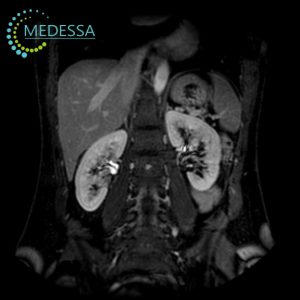

MRI of the Retroperitoneal Space

- Lower back or abdominal pain.

- Kidney function abnormalities.

- Suspected tumors or developmental abnormalities.

- Inflammatory diseases (pyelonephritis, hydronephrosis).

- Pre-surgical evaluation.